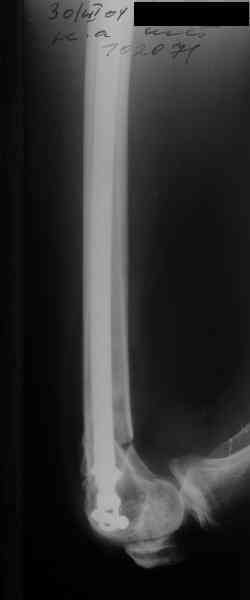

Re: Перелом диафиза и мыщелка бедра

В приложении функциональные снимки в 3 мес. и в 1 год.